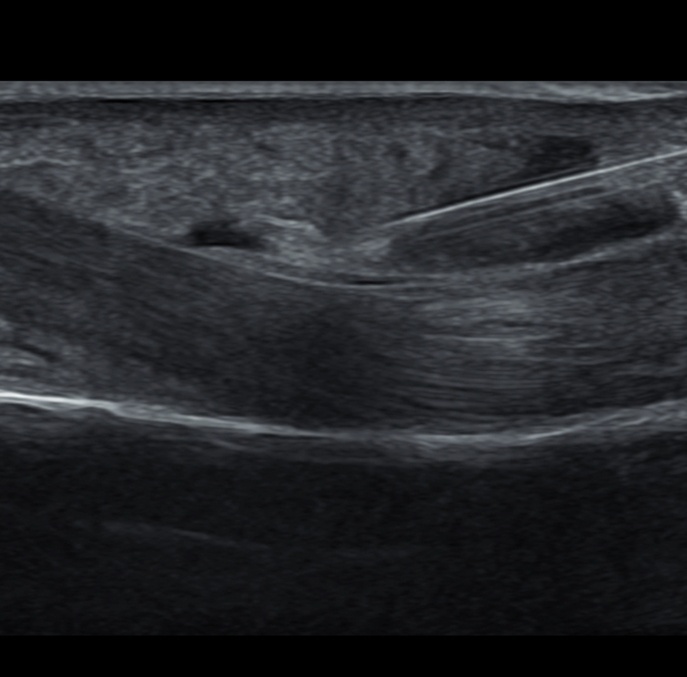

초음파유도하 주사치료

초음파로 통증 유발점을 정확하게 찾습니다.

근육 속에 발생한 미세한 통증 유발점을 정확하게 찾아내 통증부위에 직접 주사를 놓아 치료하는 방법입니다.

초음파유도하주사치료란?

초음파를 이용하여 근육 속에 발생한 미세한 통증 유발점까지 찾아내 통증이 발생한 부위에 정확하게 주사를 놓아 치료하는 방법입니다.

통증의 요인이 되는 통증 유발점을 정확히 찾고 제거하여 근육이완과 통증해소에 탁월합니다.